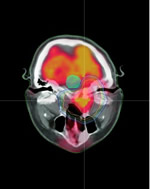

CT Simulator and Treatment Planning System with Image Fusion Capability

A CT simulation session is followed by a planning session when the customized radiation dose and physical design are made through high-end computer workstations by dosimetrists. During this process, other images (MRI, PET/CT, etc.) can be fused with our planning CT scans to precisely target the tumors and to avoid critical normal structures. When the final plan is approved by the radiation oncologists, it is transferred to the designated treatment machines for the delivery of radiation treatment.